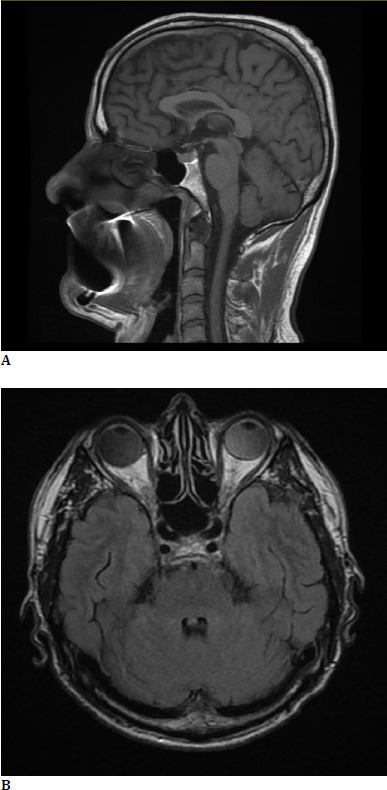

Pseudo-Foster-Kennedy syndrome presents with optic disc swelling in one eye and optic atrophy in the other eye. It differs from the true Foster-Kennedy syndrome due to the absence of an intracranial mass. One of the most common causes of pseudo-Foster-Kennedy syndrome is sequential bilateral NAION. We present the case of a male patient who came to the emergency room in our clinic complaining of sudden vision loss in his right eye, headache, and hearing loss. The patient also had a diagnosis of high amblyopia in his left eye, where we also discovered an optic atrophy. We established the positive diagnosis of pseudo-Foster-Kennedy syndrome after a thorough anamnesis, ophthalmologic examination, and multiple investigations.